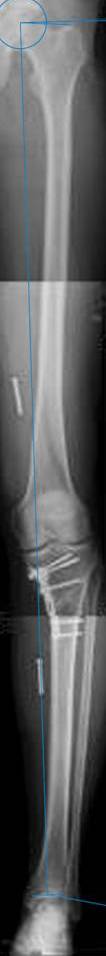

картинки оперированного пациента 40 лет, травма в 2006 году.

оперирован 06.11.2009г - корригирующая остеотомия большеберцовой кости.

Я картинку собрал с некоторыми погрешностями, если провести отвес от центра вращения головки бедра до середины голени (на пациенте),то имеется небольшой вальгус (гиперкоррекция)конечно она (гиперкоррекция) не достигает 10 гр, но 5 гр она достигает.

К сожалению, не очень удачный пример. Если верить Р-граммам, имеет место быть дисплазия мыщелков бедренной кости с наклоном суставной линии. Это уже создает сложности получения хороших отдаленных результатов. Кроме того, по классике, необходима гиперкоррекция с созданием вальгуса 7-10 градусов для максимальной разгрузки медиального отдела КС. Если верить укладке, то линия сустава имеет четкий варусный наклон, поэтому результат операции м.б. кратковременным. В этих случаях показана двойная остеотомия бедра и тибии.

Если сделать правильно, то видно, что бедренная кость в порядке, а цель остеотомии (низкой, кстати), не достигнута вовсе.

Сохраняется варус. Для того, чтобы создать вальгусную гиперкоррекцию, не моделируя при этом откровенный Х голени, можно сделать медиализирующую остеотомию.